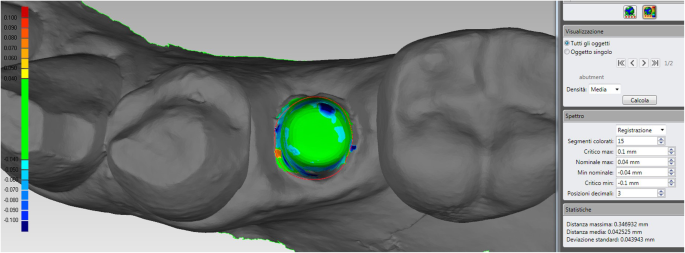

Mathematical quality

The mathematical quality of the protocol for the fabrication of the individual hybrid abutments was controlled when the superimposition of the original CAD design of the upper portion of the abutment over the mesh of the actual zirconia abutment captured intraorally was performed. In fact, the CAD files of the drawing of the individual hybrid abutment, and the mesh of the actual position of the zirconia abutment captured intraorally were saved as individual STL files after the superimposition in Exocad®, and were imported in a powerful reverse-engineering (Studio2012®, Geomagics, Morrisville, NC, USA). This software was employed to calculate the distance (mean ± SD in μm) between the visible, supramucosal surfaces of these two different STL files. In order to avoid any error given by the presence of the soft tissues, the calculation was limited to the area above the soft tissues. This type of mathematical evaluation made it possible to calculate the spatial error in the production (milling/ sintering) of the individual zirconia abutment. Finally, a digital colorimetric map was generated by the software, in order to better highlight the spatial deviations between the different files, at different levels. The threshold was set at 30 μm, so that any deviation < 30 μm was represented in green colour; deviations > 30 μm were represented in blue colour (dark blue for major deviations).

Mathematical quality of the protocol

The evaluation of the quality of the protocol for the fabrication of individual hybrid abutments revealed a mean deviation of 44 μm (± 6.3; median 45; range 28–64; confidence interval 95% 42.9–45.1) between the original CAD design of the zirconia abutment, and the mesh of the zirconia abutment captured intraorally at the end of the provisionalization (Fig. 8).

For the present case, the quality in the fabrication of the individual hybrid abutment was good, with a mean deviation of 42 μm (±43) between the original CAD design and the mesh of the zirconia abutment captured intraorally. It must be noted that the presence of a little hole on the top of the actual abutment (very useful to facilitate the outflow of the cement in excess, during the extraoral cementation in the laboratory of the upper zirconia portion on the titanium base), depicted here in dark blue, may increase the mathematical error; however, this is clinically not relevant. The software used for this calculations was a powerful reverse engineering (Studio 2012, Geomagics, Morrisville, NC, USA) able to detect deviations up to 1 μm